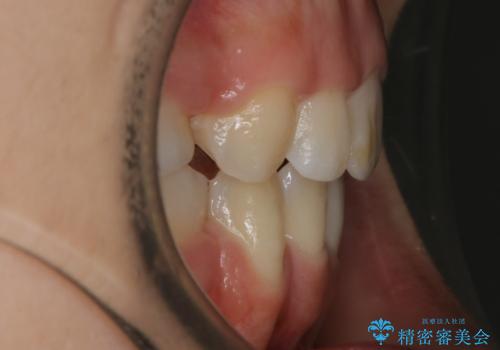

- 口元を下げたいという主訴でご来院されました。

ガタつきの度合いは軽度でしたが歯列の幅が狭く、その分前歯が上下とも前方に出てしまっていました。

しっかりと口元・顔貌まで変化を起こせるように上下左右の第一小臼歯を抜歯し、ワイヤー装置にて矯正を開始することとなりました。